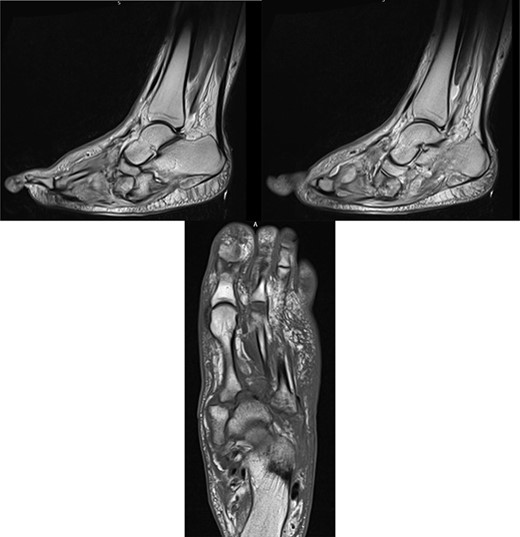

At this presentation, plain film X-ray revealed complete fracture dislocations of the second to fifth tarsometatarsal joints, involving the lateral, middle and medial cuneiform bones of the left mid-foot (Lisfranc fracture dislocations; Fig. 3). This was correlated with bone CT (computed tomography) and MR (magnetic resonance) imaging, with interval changes noted to be of rapid onset (Fig. 4).

Foot X-rays taken at acute presentation (AP and lateral views), demonstrating rapid interval progression and destruction to mid-foot.

MR images, correlating plain film findings of acute mid-foot destructive changes; typical ‘rocker bottom’ appearance of plantar aspect of foot is seen.